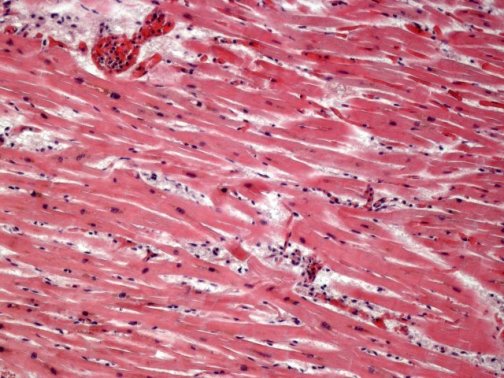

It has been several years since I last looked at pathology slides under a microscope, identifying the different cells and patterns that constitute normally functioning organs and understanding mechanically how structure dictates function. The specialized myocytes of the heart contract in an interwoven manner to orchestrate a contraction. The glandular cells of the thyroid secrete thyroid hormone. The osteoclasts and osteoblasts constantly break down and build up bone in an internal remodeling process. The uterine wall thickens and then sheds with each ovarian cycle in response to hormones. Each cell has its own purpose and works in harmony with the other cells of a specific organ to allow us to live, unaware of the constant machinery within. Pathology is the disruption of the normal structure and thus function of these cells. Diseases can be diagnosed by viewing this distortion under the microscope, in comparison to the norm.

Beyond plain sections of tissue on a slide, there are many ways to observe pathology: fluorescent staining (FISH), staining for various microbial organisms, electron microscopy to delineate finer details, as well as other methods such as radiologic exams (CT scans, PET scans, etc.) These images can be striking for two very different reasons: they can diagnose a very serious disease such as cancer, and they can be aesthetically beautiful.

In Hidden Beauty: Exploring the Aesthetics of Medical Science, a large collection of beautiful albeit pathological images are compiled to serve as both art and education. As one of the authors, pathologist Dr. Iacabuzio-Donahue, points out, most people better understand concepts when they are presented visually. A complex disease can be explained by pictures and diagrams. I find that drawing even rough representations for patients allows them to have a clearer understanding of what is going on. Showing them a CT scan of their lungs damaged by COPD is far more poignant than explaining in words what smoking does to the lungs. Likewise, showing people how the normal becomes abnormal as seen under a microscope can be very useful.